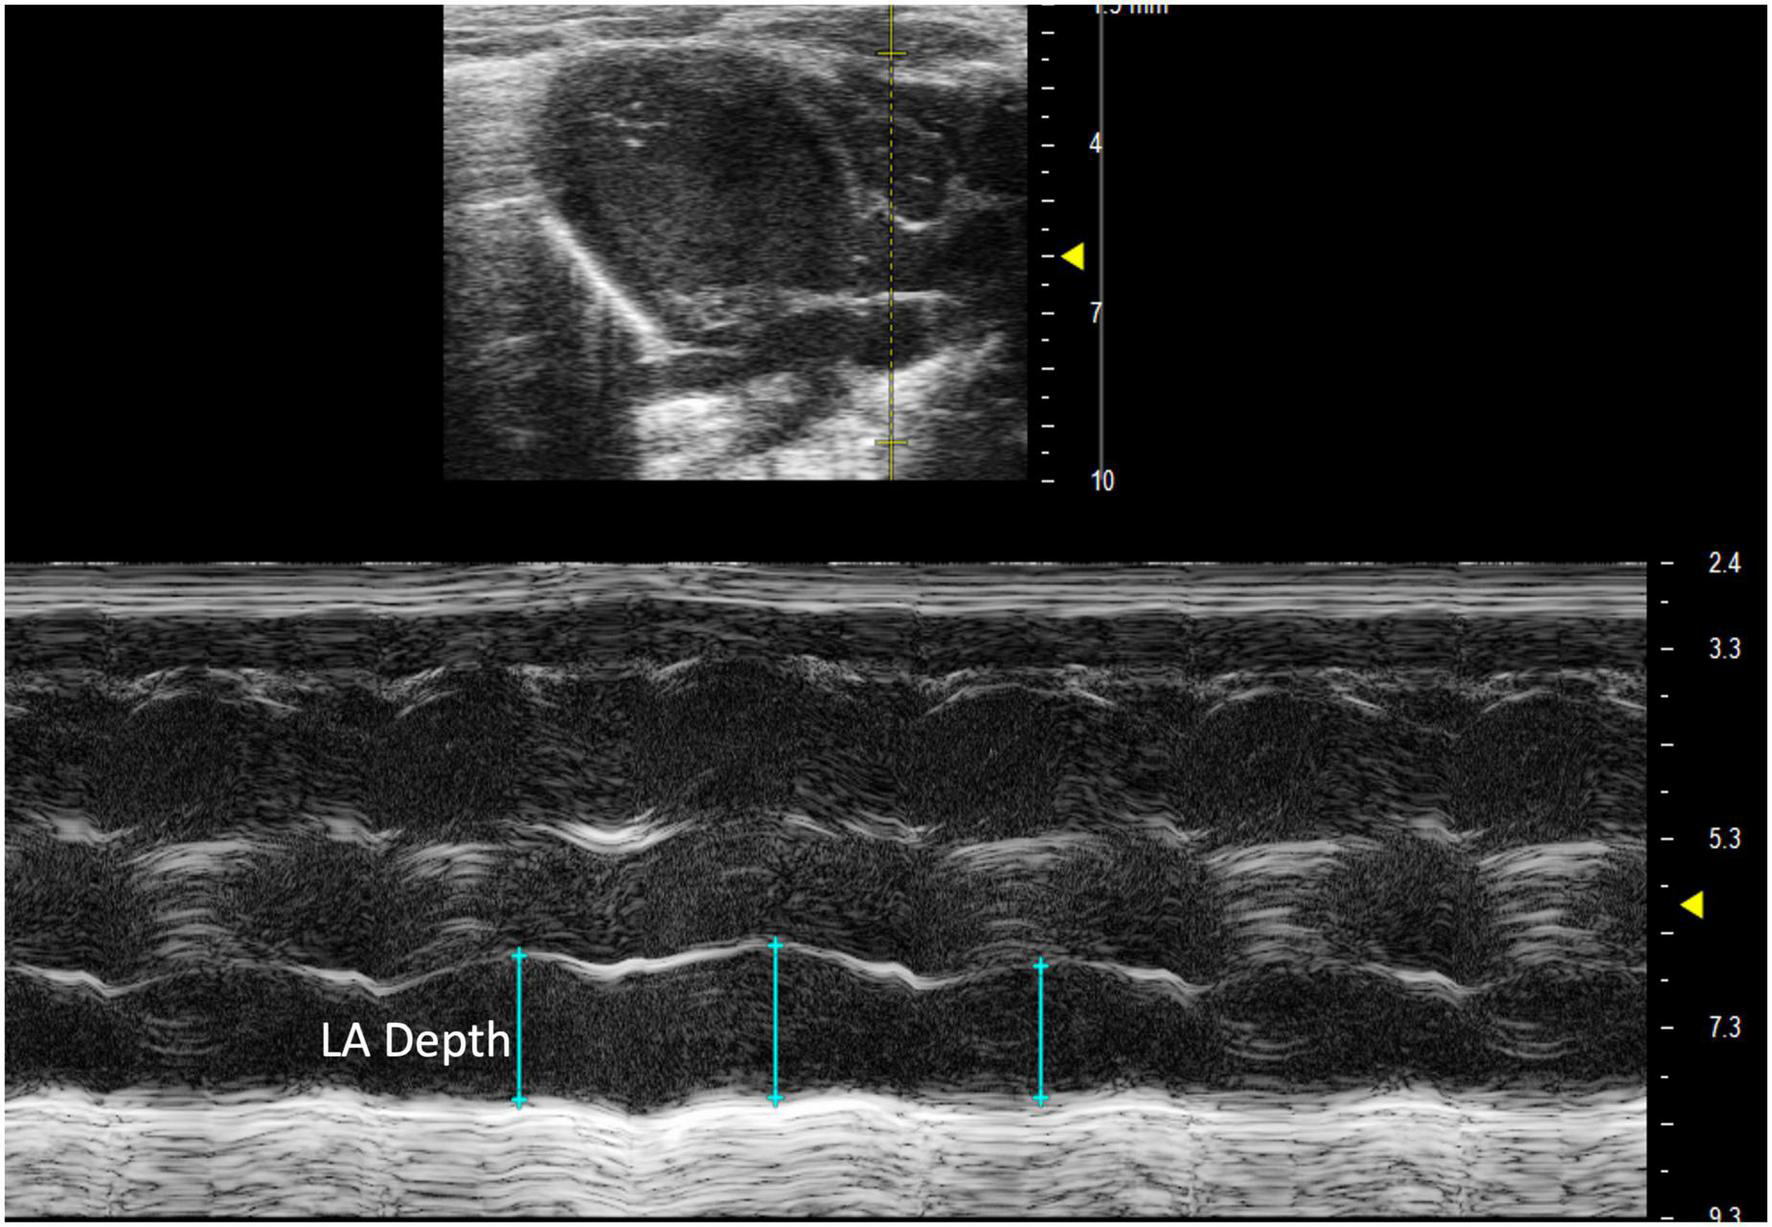

2.3.1.1 Left atrial depth

Left atrial depth can be measured vertically at end diastole. To perform this parameter, a PLAX M-mode image should be captured with the yellow line positioned over the LA, which is located inferior to the aorta (Figure 8).

FIGURE 8

Parasternal long axis (PLAX) M-mode view displaying left atrial depth measurement just inferior to the aorta.